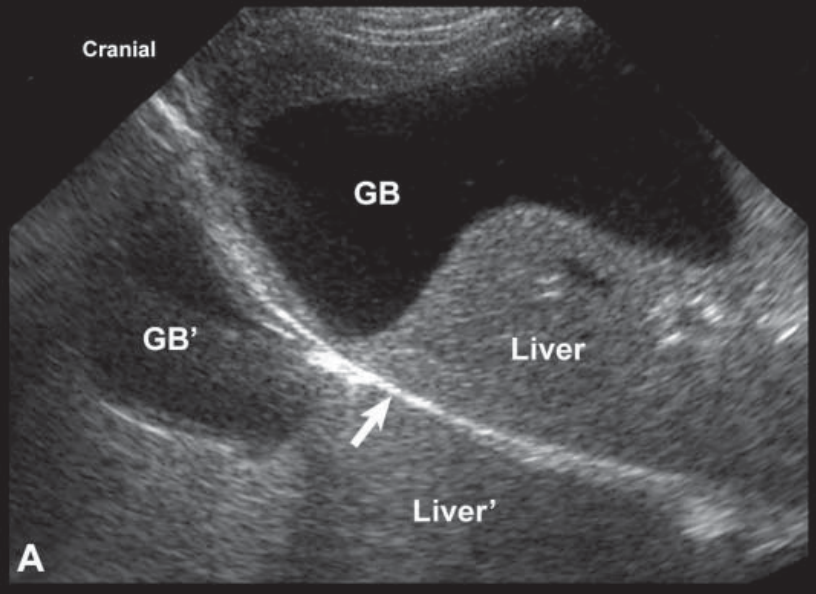

Name this artifact.

What is the cause of the artifact?

Mirror image artifact: Created when sound reflects off a strong reflector and is redirected toward a second structure (target), where it then reflects back to the first reflector, then back up to probe. This creates a second image of the target in the path of the original beam and deeper than the actual target